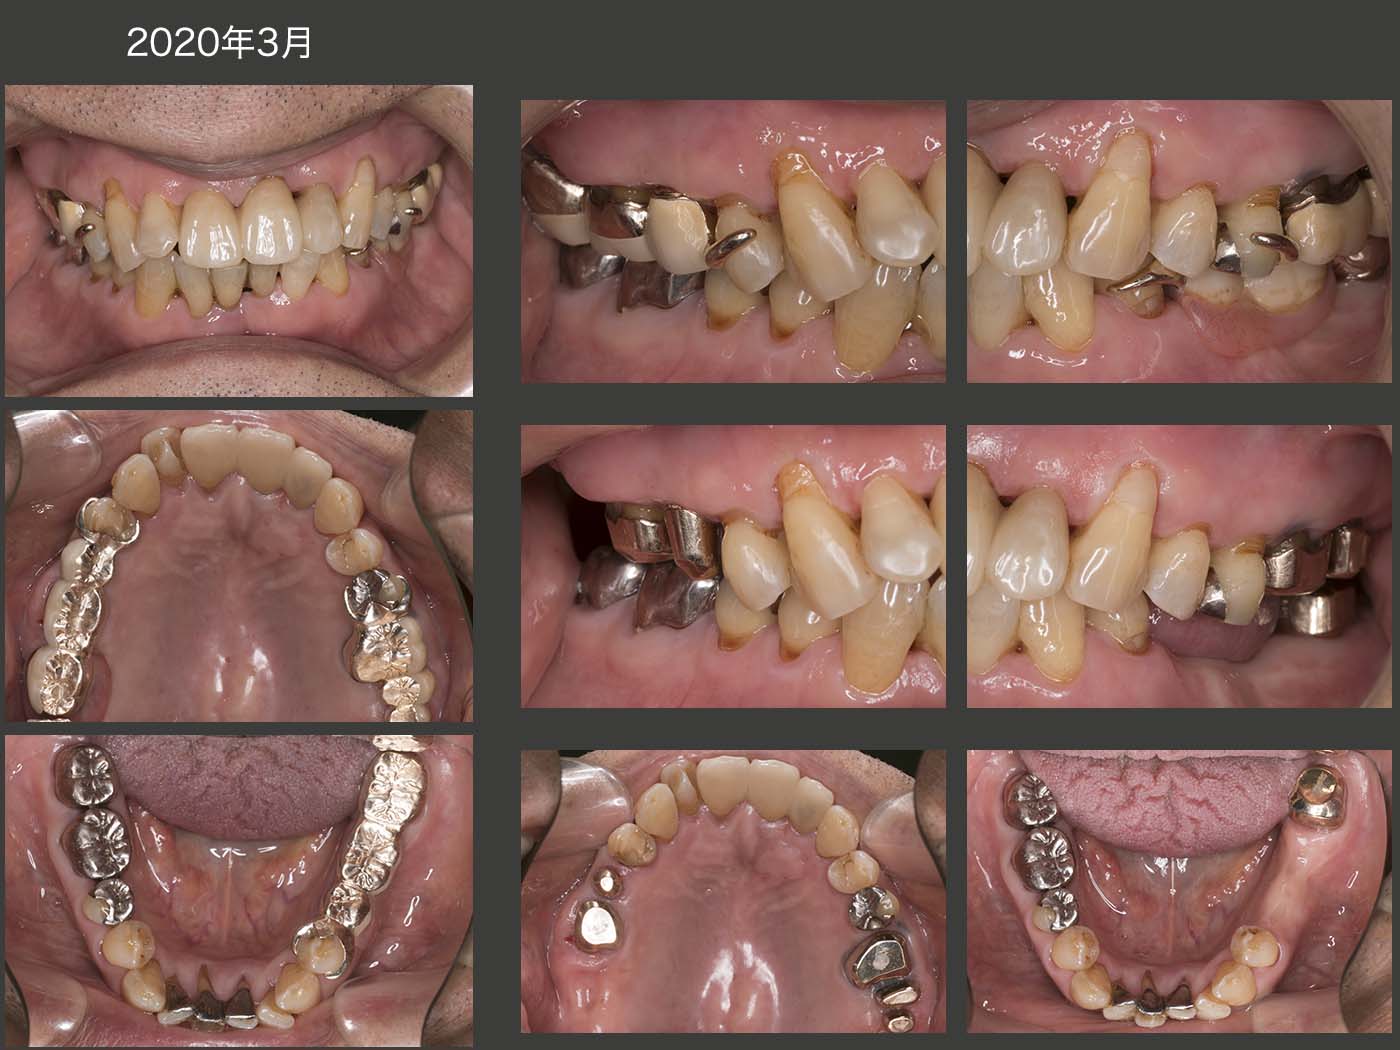

2016年7月,初診終了時の状態.右上7(移植歯)の歯周ポケットは最大5mmの値を示した.左上1は初診時より最大9mmの歯周ポケットがみられたが,歯周基本治療以外,特に治療を施していない.その他の残存歯に問題はみられなかった.なお,初診終了時の残存歯の分布から右側が習慣性咀嚼側になることが予想できる.